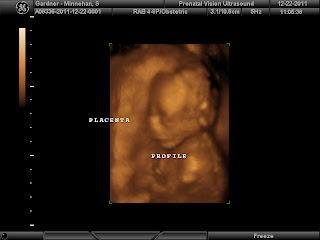

13 Weeks - Baby: Baby is about 3 inches long and weighs in at an ounce (think shrimp-like!) Fingerprints have formed, blood vessels are visible through the skin and the body is catching up in proportion to the head! If it's a girl, she has about 2 million eggs in her ovaries. The heartbeat was again in the 160s and the doctor made a speculation about the gender; he was 75% sure it's a girl! GIRL, omg, I had to know for sure! With the holidays coming up and things going on sale after Christmas, I just had to know! How was I supposed to keep that a secret unti at least Thanksgiving and how was I supposed to get through the rest of the semester without getting distracted?! I'll tell you it took both Ryan and I an incredible amount of discipline not to spill the beans and we decided to get a 3D ultrasound three days before Christmas so we could share with our families!

Upcoming: Multiple marker screening in week 14, 3D ultrasound to confirm gender in week 19 (thanks in part to my parents who split the cost with us and were able to attend!)

The next post will confirm the gender and share some pictures and the video if I can figure out how to upload it!